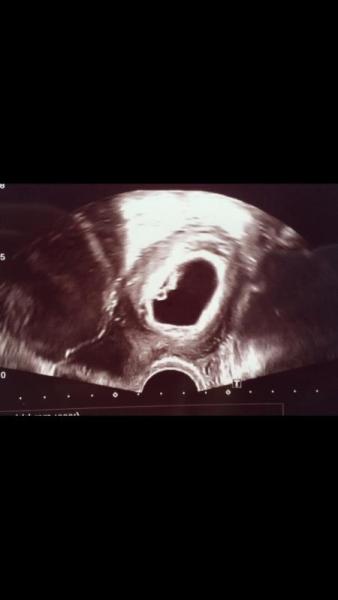

Wir durften heut zum ersten Mal das blubbern sehen. Ich bin ganz verliebt in meine kleine Bohne. Jetzt heißt es wieder 3 Wochen warten. Hoffe euch und euren Bauchbewohnern geht es allen gut. Liebste Grüße

Foto vergessen ;)

Bild zu